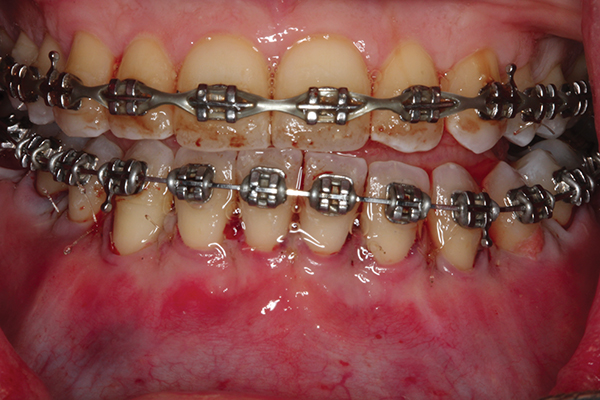

Fig 3. Corticotomy cuts performed.

Figure 3